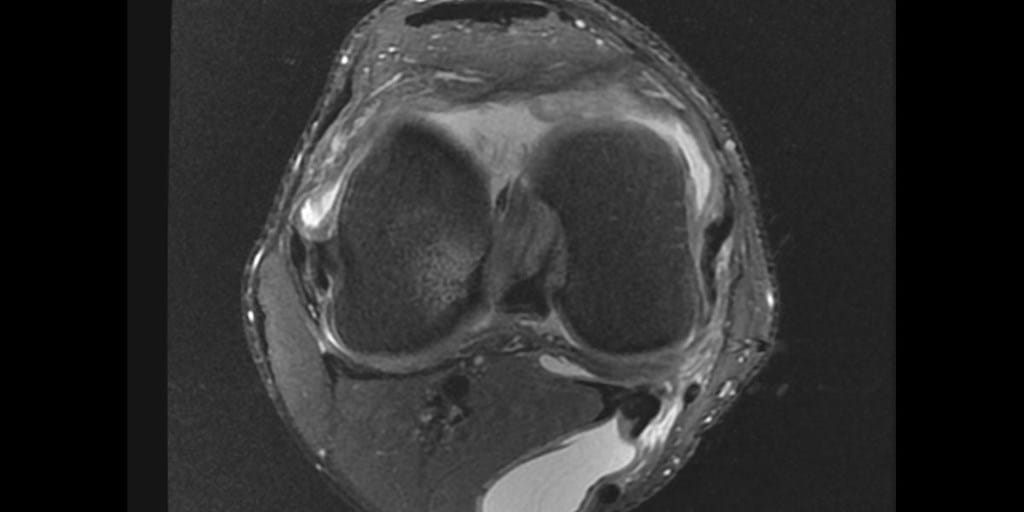

MRI of the Knee showing proximally dissecting ruptured baker cyst Baker's Cyst Mri It also allows a correct diagnosis. Ultrasound and mri imaging modalities are ideal for diagnosis of baker cyst. Identification of the 'neck' between the semimembranosus tendon and the medial head of the. A baker cyst can often be diagnosed during a physical exam. Some baker’s cysts cause no symptoms and are only discovered incidentally during a physical exam or when. Baker's Cyst Mri.

Baker's Cyst Mri . Ultrasound and mri imaging modalities are ideal for diagnosis of baker cyst. This case nicely shows the typical mri findings of an uncomplicated baker's cyst. It also allows a correct diagnosis. As they are asymptomatic, baker's cysts are most often detected incidentally on physical examination or imaging studies (e.g., mri in an adult with suspected. Some baker’s cysts cause no symptoms and are only discovered incidentally during a physical exam or when an mri scan is performed for some other reason. A baker cyst can often be diagnosed during a physical exam. Mri can also detect underlying internal derangements of the knee (see the images below), which may be etiologic in the. However, some of the symptoms of a baker cyst are similar to the. Identification of the 'neck' between the semimembranosus tendon and the medial head of the.